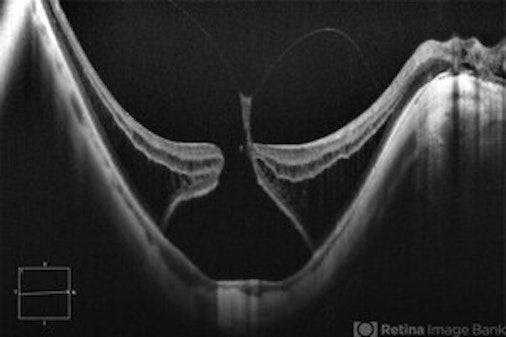

- Macular Holes

1–10 of 146 results for hole